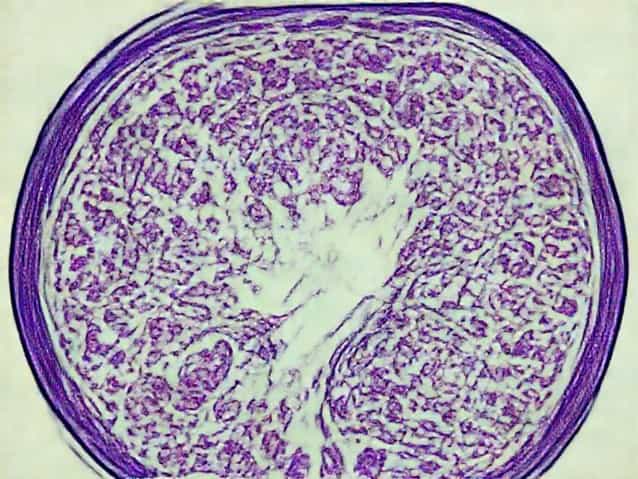

Under the microscope, low grade serous carcinoma typically shows papillary or micropapillary structures. These finger-like projections are lined by tumor cells in an orderly fashion.

Solid sheets of cells are uncommon, which helps differentiate it from more aggressive tumors.

Psammoma Bodies

Psammoma bodies are round, calcified structures often seen in serous tumors. They are commonly present in low grade serous carcinoma.

While not exclusive to this cancer type, their presence adds supportive evidence during microscopic evaluation.